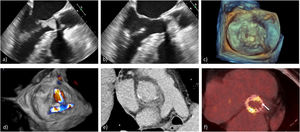

La ecocardiografía transtorácica (ETT), a pesar de su discreta sensibilidad (30% en el caso de vegetaciones y 36% en afectación periprotésica), tiene una elevada especificidad (>90%), similar a la de la ecocardiografía transesofágica (ETE)82,83 (figs. 2a y b).

Endocarditis protésica: a) ETE-2D: vegetación protésica aórtica en tracto de salida del ventrículo izquierdo en diástole, b) la misma vegetación con protusión sistólica en la aorta, c) ETE-3D vegetaciones en EPV mitral, d) ETE-3D: fuga periprotésica en EPV mitral, e) TC cardiaca, corte axial: absceso periprotésico aórtico y f) PET con 18F-FDG: hipercaptación multifocal y heterogénea sobre TAVI balón-expandible.

La ETE se indica en los pacientes con ETT negativa o para caracterizar la extensión local de la infección por su mejor desempeño para la detección de vegetaciones de pequeño tamaño, complicaciones periprotésicas o infección de dispositivos electrónicos implantables6,84, con una sensibilidad y especificidad del 85-90% y 90-100%, respectivamente85, que serían del 87 y 95% en el caso de extensión local86,87. A pesar de ello, todavía existen variabilidades acerca de su utilización88 y según datos de EURO-ENDO, el 99,8% de los pacientes diagnosticados de EI tienen un ETT (156 hospitales de 40 países). Sin embargo, solamente el 58,1% han realizado ETE (66 vs. 53% EPV vs. EVN; p<0,0001). La sombra acústica del material protésico puede ser una limitación, sobre todo en la cara anterior de la raíz aórtica83, al igual que la presencia de hilos de sutura, restos del aparato subvalvular mitral o hematomas periaórticos, que requieren de contextualización clínica60. La ETE-3D (fig. 2c), aunque no como herramienta inicial, ha demostrado utilidad complementaria, combinada con la ETE-2D89, para caracterizar las complicaciones periprotésicas (localización, tamaño, extensión), gravedad de lesiones y perforaciones90. La ecocardiografía debe realizarse tan pronto como exista sospecha, ya que las complicaciones locales o embólicas aumentan paralelamente al tiempo transcurrido desde la primera ecocardiografía91.

La tomografía computarizada (TC), la resonancia magnética (RM) y la radiología nuclear proporcionan imágenes complementarias que ayudan a confirmar o descartar, así como a delimitar la extensión local y las complicaciones extracardíacas92. La TC cardiaca, es una herramienta fiable para la evaluación de extensión periprotésica (fig. 2e) y complementado con imágenes de medicina molecular juegan un papel relevante en la EPV11,93 mediante su integración en flujos de trabajo de imagen multimodal69.

Las técnicas de medicina molecular no se basan en el análisis morfológico, sino en la actividad metabólica y son útiles en enfermedades oncológicas, infecciosas e inflamatorias95,96. La tomografía por emisión de positrones (PET) con 18F-Fluorodesoxiglucosa (FDG), combina la información anatómica de la TC con la captación metabólica de FDG (fig. 2f). En fiebre de origen desconocida presentan una sensibilidad del 88% y una especificidad del 100%97. En la EPV la sensibilidad es elevada, del 85% aproximadamente (73-100%)7,98. En la EVN su utilidad es controvertida, por la baja sensibilidad99,100, limitándose a la detección de embolias como criterio menor. En la serie de Saby et al. para EPV la sensibilidad y la especificidad han sido del 73 y 80%, respectivamente, que aumenta al 92 y 100%; mejorando el rendimiento diagnóstico cuando se utiliza sincronizado con el electrocardiograma y en combinación con ETE, permitiendo reclasificar a un 20% de los pacientes101. Ha demostrado utilidad en la detección de lesiones metastásicas por embolia séptica en órganos con baja actividad metabólica (tejido músculo esquelético o bazo)102. La importancia de esta modalidad en el diagnóstico de infecciones de dispositivos electrónicos intracardiacos es creciente, ya que permite, además, localizar la infección en la bolsa o en los electrodos103,104. Sin embargo, requiere preparación con dieta baja en hidratos de carbono y rica en grasas durante las 72h previas. La administración previa de antibióticos y/o hiperglucémica pueden dar falsos negativos95,105, como en los pacientes diabéticos descompensados106. La cirugía cardíaca reciente y trombosis86 resulta en falsos positivos.